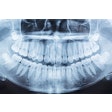

Pearl's artificial intelligence (AI)-based dental x-ray analysis software, Second Opinion, will be integrated into CareStack's practice management system.

Second Opinion assists dentists in detecting common dental conditions through the analysis of bitewings and periapical x-rays of patients ages 12 and older. Also, the integration provides CareStack users access to Pearl's clinical performance AI platform, Practice Intelligence.